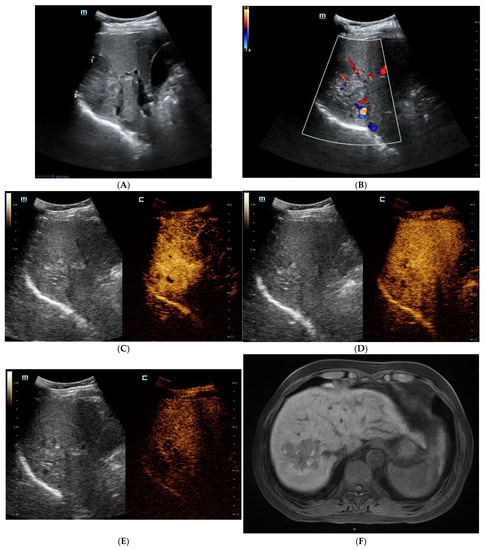

Figure 1.

The contrast-enhanced ultrasound (CEUS) and contrast-enhanced magnetic resonance imaging (CEMRI) of steatohepatitic hepatocellular carcinoma (SH-HCC). A heterogeneous hyperechoic le-sion was detected in the right lobe of the liver (A). Short linear blood flow signals were seen in the peripheral of mass (B). As seen via CEUS, the hepatic nodule did not show rim, peripheral dis-continuous or heterogeneous hyperenhancement in the early arterial phase (C). During the portal venous phase, it was continuous iso-enhancement (D). It exhibited mild washout in the late phase (E). The hepatic lesion was heterogeneous hypointense on T1WI (F). A signal drop in the T1WI opposed-phase was observed (G). It was marked as hyperintense on unenhanced T2WI (H). After injection of contrast agent, the hepatic lesion showed non-rim hyperenhancement in the arterial phase (I). It became hypo-intensity during the late phase (J).